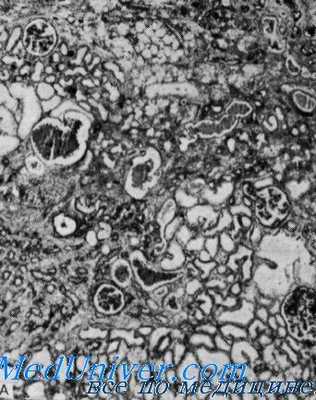

Патология. Биопсия почки пробанда обнаружила склероз клубочков. Интерстициальпая ткань была интенсивно инфильтрирована лимфоцитами. В артериях нашли различную степень гипертрофии срединной оболочки и субэндотелиального склероза. Электрономикрофотографии выявили утолщение срединной соединительнотканной сосудистой оболочки. В межклеточном веществе — плотные отложения.